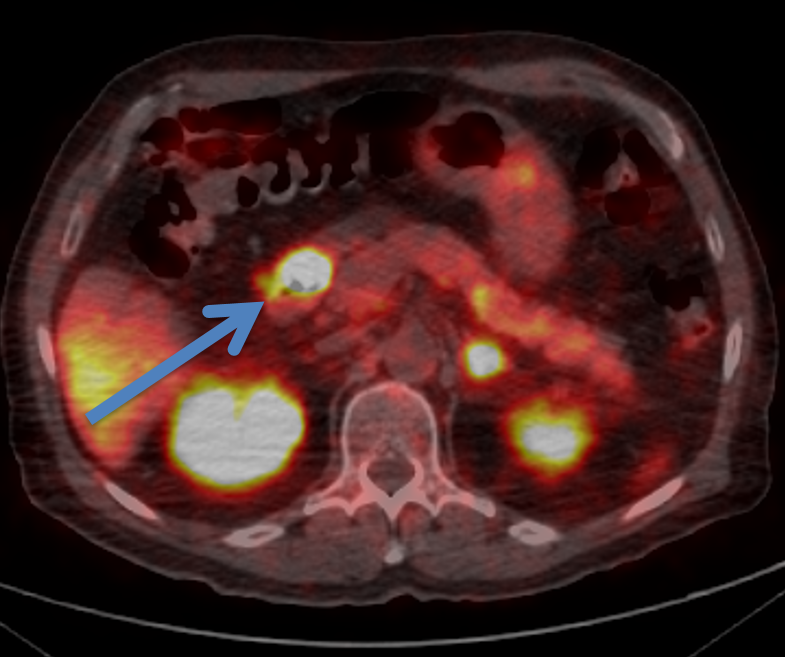

- PET Dotatate is helpful for staging well differentiated neuroendocrine tumors

These highly vascular tumors classically show enhancement on arterial phase.

Neuroendocrine tumor is in the differential for hypervascular liver metastasis. Remember the mnemonic “CT/MRI”.

Choriocarcinoma, thyroid cancer, melanoma, renal cell carcinoma, and islet cell tumor (neuroendocrine tumor)